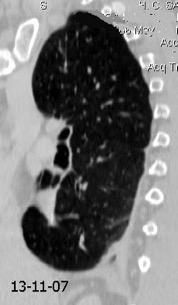

Post infarto 1-7 % (Dressler)

Trauma cerrado Implantación marcapasos

Cirugía cardiaca. 17-31% (Post.pericardiotomía)

3707 pacientes 29 Derrames (0,78%) > de 25% del hemitórax

Todas menos 2 Izdos.

Angioplastia

By-pass coronario 21-10-03